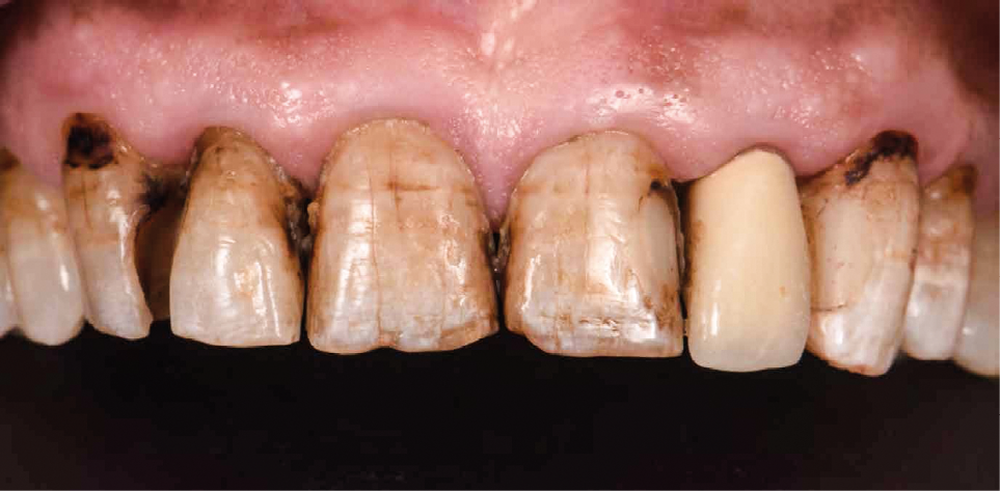

Un patient, âgé de 62 ans, nous consulte pour la réhabilitation de son sourire qu’il trouve disgracieux. Il est gêné par la longueur et l’aspect opaque de son incisive latérale supérieure gauche et, de manière générale, par la couleur et les fêlures présentes sur ses dents antérieures maxillaires.

On note la présence d’anciennes restaurations composites, de lésions carieuses actives et de pertes de substances amélo-dentinaires (fig. 1).

La deuxième étape comprend la préparation dentaire et la réalisation de restaurations provisoires (Voco Structur®) issues du wax-up. On traitera les lésions carieuses et les composites déjà présents seront remplacés. Les préparations sont donc guidées par ces restaurations de manière à n’avoir qu’une seule interface « céramique/dent » (fig. 3). On note donc des facettes à retour palatin, une couronne périphérique, et des couronnes ¾. La restauration corono-radiculaire sur 22 n’est pas déposée pour deux raisons : aucune lésion apicale n’est présente sur la dent et le patient est porteur d’une prothèse valvulaire aortique contre-indiquant tout retraitement endodontique (haut risque d’endocardite infectieuse).